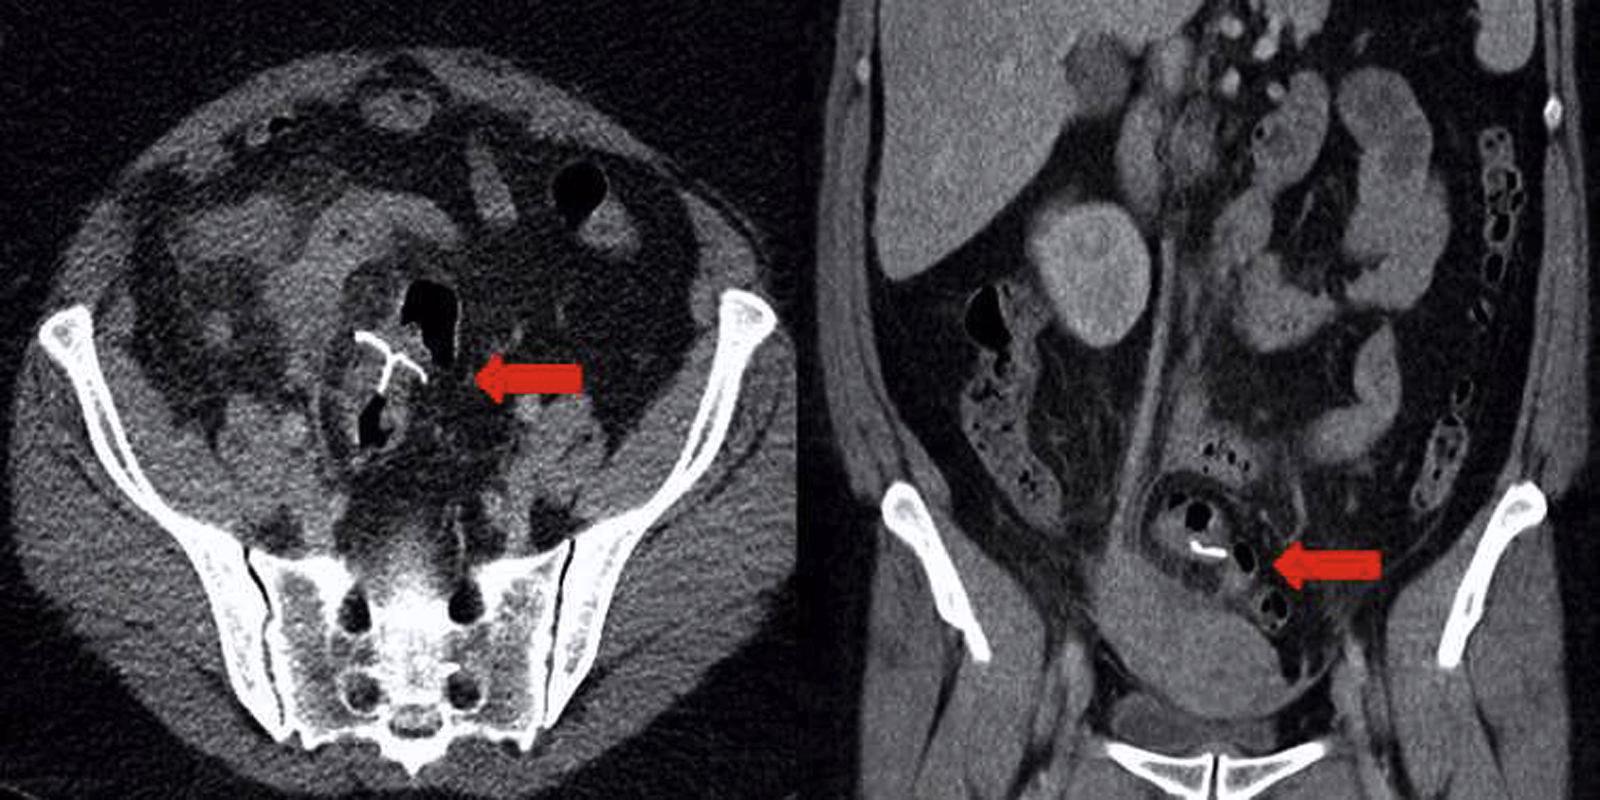

- Ecografía: En algunos casos, se puede realizar una ecografía para observar los órganos pélvicos y descartar otras afecciones.

El tratamiento para la EIP se basa en el uso de antibióticos para eliminar las bacterias causantes de la infección. Es vital comenzar el tratamiento lo antes posible para evitar complicaciones a largo plazo. Una pregunta frecuente es si se debe retirar el DIU. Si los síntomas mejoran rápidamente con los antibióticos (generalmente en las primeras 48-72 horas), a menudo no es necesario retirar el dispositivo.